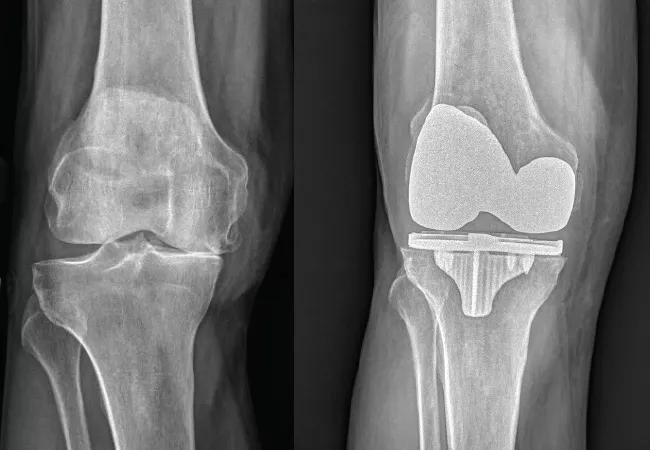

Degree of Obesity Relates to Risk of Post-Operative Complications in Hip and Knee Arthroplasty

The risk of developing major complications in the first 30 days following lower-extremity joint arthroplasty may be related to the severity of obesity, according to a new series of studies. The work suggests that, when it comes to evaluating surgical risks, it might be more accurate to consider body mass index (BMI) as a continuum rather than as a binary, with different weight categories correlated to different levels and types of post-operative complications. Understanding the interaction between BMI and complications is one way in which physicians are working to improve surgical outcomes.

In total knee arthroplasty, overweight patients had no higher overall complication risks than patients with BMIs in the normal range. However, obese patients had an increased risk of developing a pulmonary embolism, and morbidly obese patients had increased risks of readmission, reoperation, superficial infection, periprosthetic joint infection, wound dehiscence, pulmonary embolism, urinary tract infection, reintubation and renal insufficiency.

In unicompartmental knee arthroplasty, BMI does not appear to impact a patient’s risk of developing 30-day complications, with the exception of one: morbidly obese patients did have an increased risk of developing superficial surgical site infection.

In total hip arthroplasty, increased BMI was correlated to increased readmissions, reoperation, superficial infection, prosthetic joint infection and sepsis.

In terms of revision surgeries, there was a linear relationship between BMI and readmission and reoperation rates. Obese patients had a lower risk of organ/space surgical site infection compared to normal weight patients. Morbidly obese patients, however, had an increased risk of developing superficial SSI. For knee surgery, the lowest rate of complications occurred in patients with a BMI of approximately 30 kg/m2. For hips, the lowest rate occurred for patients with a BMI of 28 kg/m2.